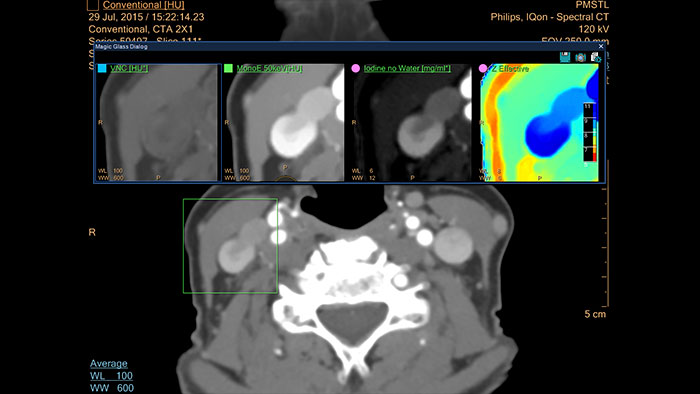

CT Spectral Light Magic Glass

Review spectral data in a range of not spectral-enhanced CT applications

Allows retrospective use of spectral data that was saved in a series of spectral base images (SBI).

The fast launch of LMG allows review and identification of the most relevant results to be launched into the application for further analysis.

• The option is available from the following applications: Brain Perfusion, Functional CT, Liver Analysis, PAA, TAVI, Acute Multifunctional Review, Virtual Colonoscopy.

• Spectral Magic Glass can be launched only for CT images or images created on the Philips IQon Spectral CT.

CT Spectral Magic Glass on PACS*

IQon Spectral CT Functionality

IQon Spectral CT is the only scanner to offer CT Spectral Light Magic Glass and CT Spectral Magic Glass on PACS, helping radiologists review and analyze multiple layers of spectral data at once, including on their PACS.

• On-demand simultaneous analysis of multiple spectral results for an Region Of Interest (ROI).

• Integrates into a health system’s current PACS setup for certain PACS vendors.

• Spectral results viewable, during a routine reading.

• Enterprise-wide spectral viewing and analysis allows access to capabilities virtually anywhere in the organization.

* Standard with the CT Spectral option on IntelliSpace Portal.